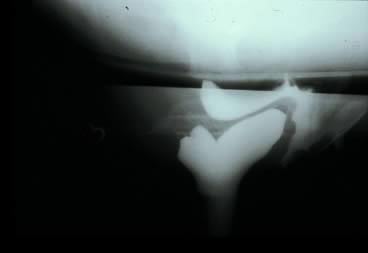

Before starting any rectocele repair, the surgeon should approximate the introitus by using Allis clamps bilaterally to help determine how much perineal and vaginal tissue needs to be excised to correct any gaping of the introitus. The repaired opening should accommodate three fingerbreadths, taking into account that the levator ani and perineal muscles are relaxed from general anesthesia and may constrict further postoperatively and with postmenopausal atrophy. The next step is to place Allis clamps on the posterior perineum; a diamond-shaped perineal incision is made, and the overlying skin is removed. The length and width of the perineal incision depend on the epithelium needed for restoration of the perineal body. Metzenbaum scissors are used to develop a plane in the rectovaginal space. An effort is made to leave as much fascia on the rectum as possible. Sharp dissection usually is required over the perineal body because of previous scarring from episiotomies. The surgeon performs blunt and sharp dissection between the mucosa and fascia to the apex of the vagina. This dissection is continued laterally to the tendinous arch of the levator ani and extends inferiorly to the perineal body. When hemostasis is ensured, irrigation may be performed to attain a clean operative field to allow inspection for defects. The rectovaginal fascia is inspected for defects by the surgeon inserting a finger of the nondominant hand into the rectum (Figs 4 and 5).

Fig. 4. Transverse and vertical defect detected on rectal examination.

Fig. 5. High transverse midline fascial defect.